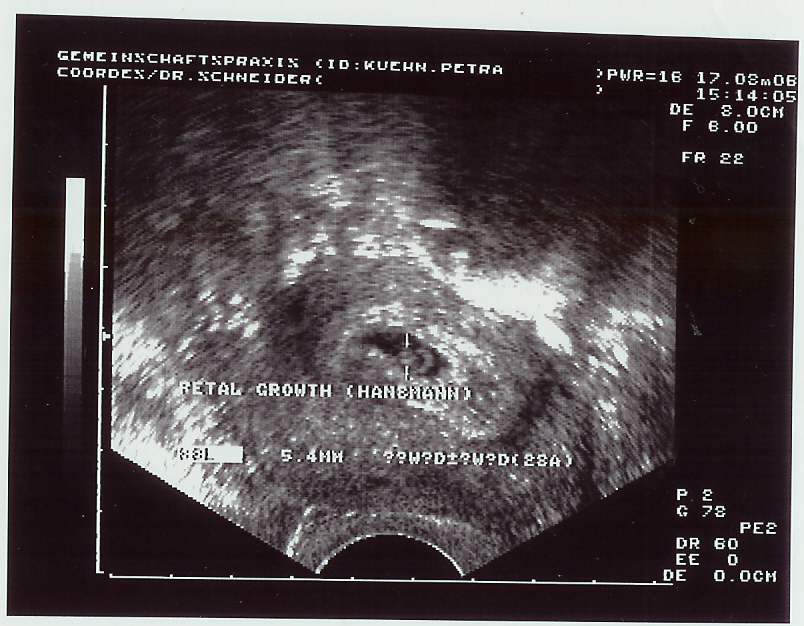

der schönste "schwarze Fleck" der Welt....den man da sehen kann....